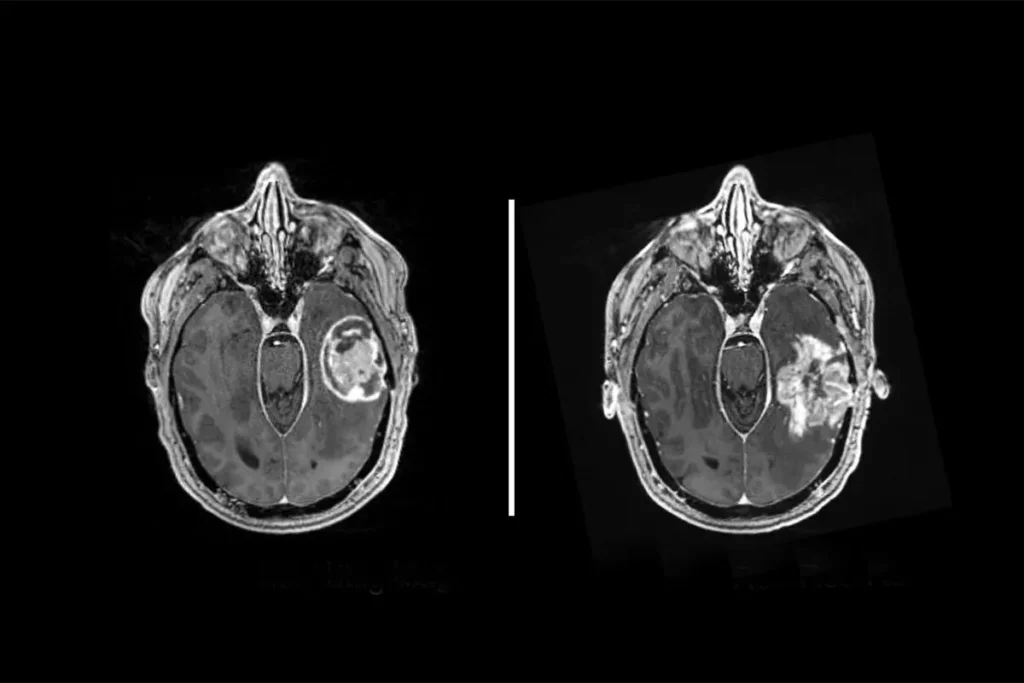

Diagnosis

- MRI with contrast (gold standard)